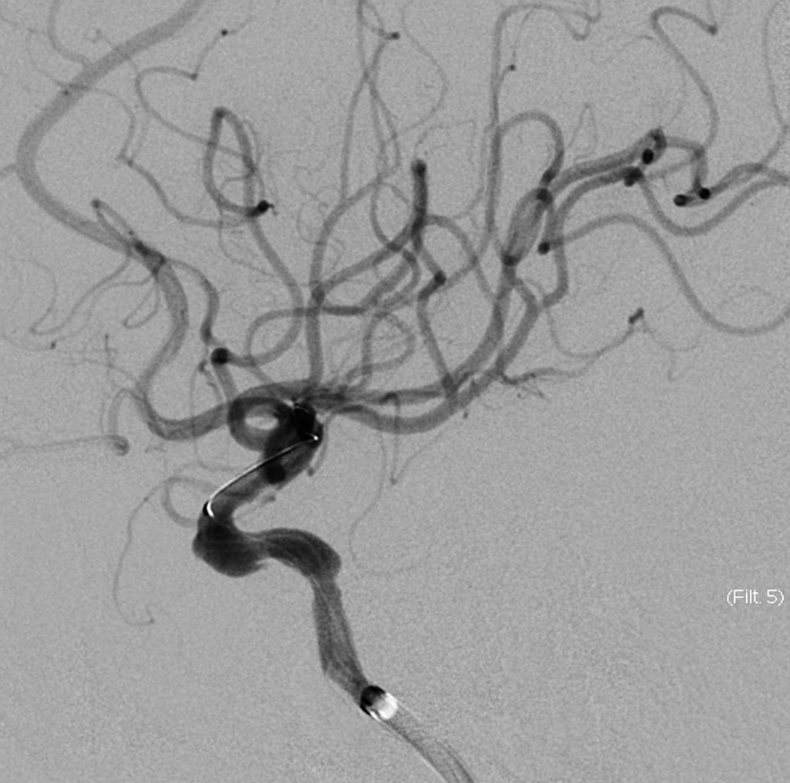

脑血管造影提示右侧颈内动脉颅内段多发动脉瘤(反主动脉弓)

脑血管造影提示右侧颈内动脉颅内段多发动脉瘤

4mm×30mm Streamline

术后4月余随访:多发动脉瘤均未见显影,远端残余轻度狭窄

术前术后对比